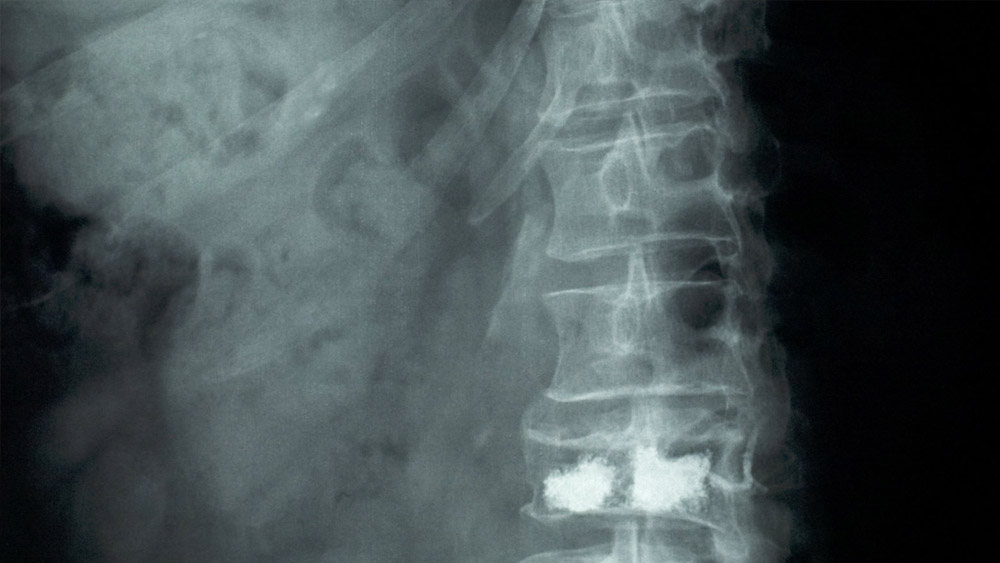

২০১৭ সালে মোটরবাইক দুর্ঘটনায় শিরদাঁড়ার একাধিক হাড়ে চিড় ধরে গিয়েছিল ইন্দুবেনের। সেখানকার স্নায়ুতেও সমস্যা দেখা দিয়েছিল।

২০১৭ সালে মোটরবাইক দুর্ঘটনায় শিরদাঁড়ার একাধিক হাড়ে চিড় ধরে গিয়েছিল ইন্দুবেনের। সেখানকার স্নায়ুতেও সমস্যা দেখা দিয়েছিল। চিকিৎসকদের পরামর্শ ছিল, পুরোপুরি শয্যাশায়ী হয়ে থাকতে হবে। তা না হলে তাঁর পিঠের সমস্যা চিরকালের জন্য নিয়ন্ত্রণের বাইরে চলে যাবে।

শিরদাঁড়ার সমস্যা মেটাতে ইন্দুবেনের অস্ত্রোপচার করতে হয়েছিল। তবে তার পরেও চিকিৎসা চালিয়ে যেতে হত। সেই খরচের বোঝা চেপে বসেছিল ইন্দুবেনের পরিবারে। তিনি বলেন, ‘‘আমার মেয়েরা বেসরকারি স্কুলে পড়ে। সে খরচের পাশাপাশি সংসারের পাঁচটা মুখে অন্ন জোগাতে হয়। স্বামীর একার রোজগারে কোনও ভাবেই আমারা কুলিয়ে উঠতে পারছিলাম না। এক সময় মনে হয়েছিল যেন একটা অন্ধকার টানেলে রয়েছি, যেখানে আলোর আভাসও নেই।’’